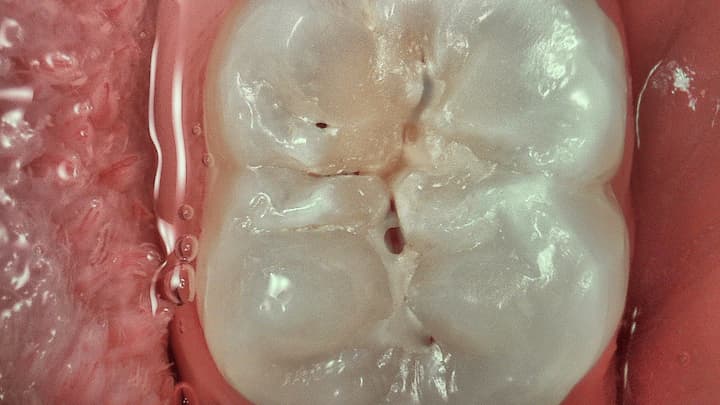

Daylight mode

Rejestrowanie naturalnych kolorów w celu lepszej interpretacji widocznego odcienia zębów, identyfikacji patologii i obserwacji pacjenta.

Daylight+ mode

Wysokie kontrasty podkreślające bruzdy anatomiczne oraz uwydatniające szczegóły struktury/głębokości zębiny.